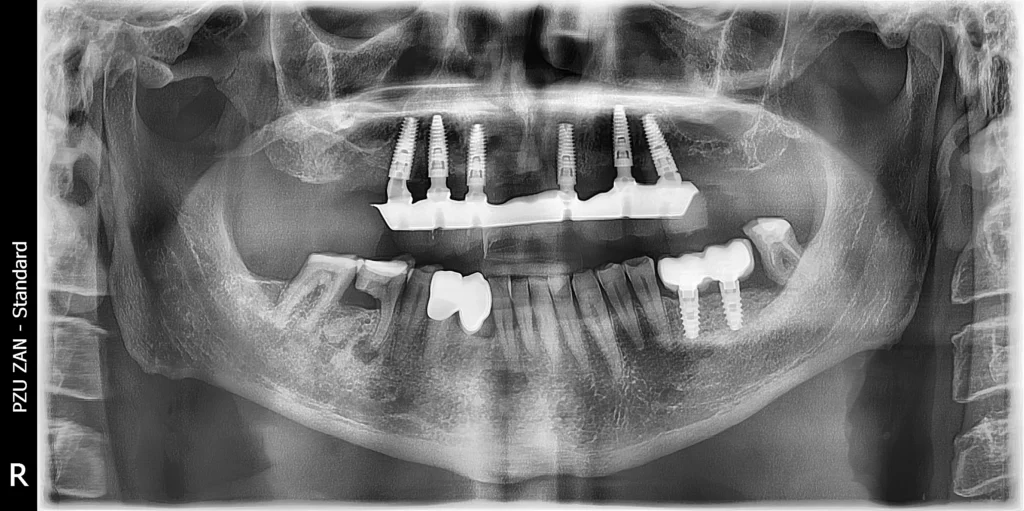

This patient came to our clinic with a severe problem in his upper jaw. He had bridges and crowns made 20 years ago, but the construction was failing and all the teeth were moving.

After a detailed analysis a therapy plan was provided. All the teeth needed to be removed and the solution was an all-on-6 treatment with dental implants.

With a digital workflow we created a surgical guide, extracted all the teeth and immediately placed the dental implants using the surgical guide. The patient was provided with temporary teeth the next day.